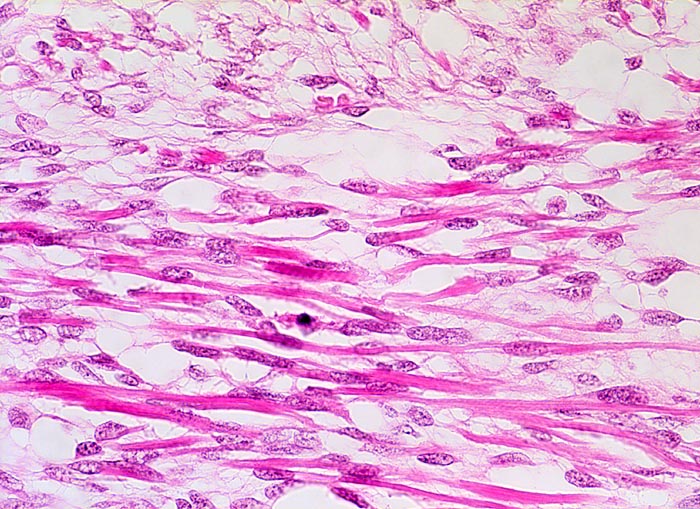

Neben spindeligen Stromazellen finden sich längliche Zellen mit hypereosinophilem Zytoplasma mit Querstreifung (Skelettmuskeldifferenzierung)

Die Stromazellen sind meist fibrozytisch oder myxoid, nicht selten findet man aber auch Skelettmuskeldifferenzierung. Selten sind andere heterologe Elemente wie Plattenepithel, glatter Muskel, Fettgewebe oder Knorpel vorhanden.